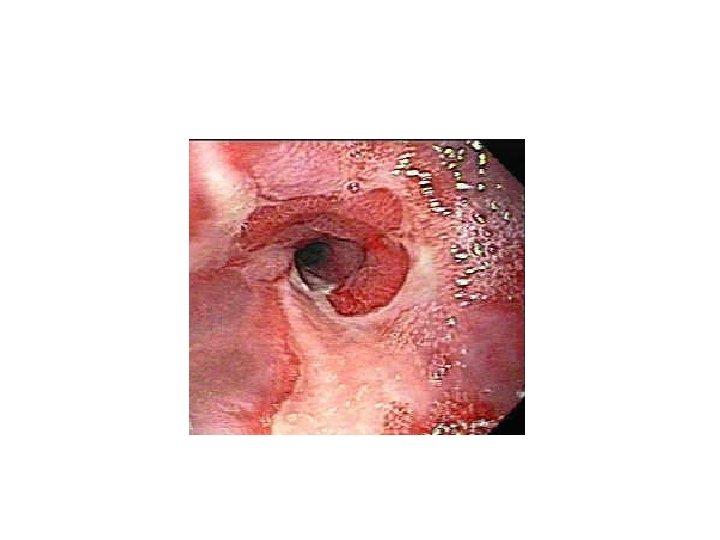

ESÓFAGO: VARICES • ANATOMÍA PATOLÓGICA: – Normalmente se diagnostica mediante endoscopia o postmortem – Aparecen en los vasos del 1/3 distal del esófago – Venas dilatadas y tortuosas – Mucosa irregularmente abollonada, violácea – Erosiones y úlceras superficiales en la mucosa – Si se han roto, restos hemáticos adheridos a la pared del esófago

ESÓFAGO: VARICES • El plexo esofágico permite la comunicación entre la circulación esplácnica intraabdominal y la circulación venosa. – Si se impide el reflujo sanguíneo portal al hígado, ocurre la hipertensión portal • El flujo sanguíneo portal se desvía a través de las venas del estómago al plexo esofágico, y de ahí a la vena ácigos y a la cava superior • La cirrosis hepática es causa importante de hipertensión portal – el aumento de la presión en el plexo esofágico produce dilatación de los vasos (varices)

ESÓFAGO: VARICES • SÍNTOMAS: – Generalmente asintomático hasta que se rompen – La rotura de varices esofágicas produce una hemorragia masiva y la adhesión de la sangre a la pared del esófago. • • CAUSA DE RUPTURA – – • La mitad de muertes en los cirróticos avanzados se debe a rotura de las varices esofágicas Adelgazamiento del epitelio esofágico que las recubre Ulceración el epitelio Incremento de la presión intravascular Vómitos TRATAMIENTO: – Taponamiento con balón intraesofágico – Escleroterapia • MORTALIDAD: – 30% mortalidad en el primer episodio